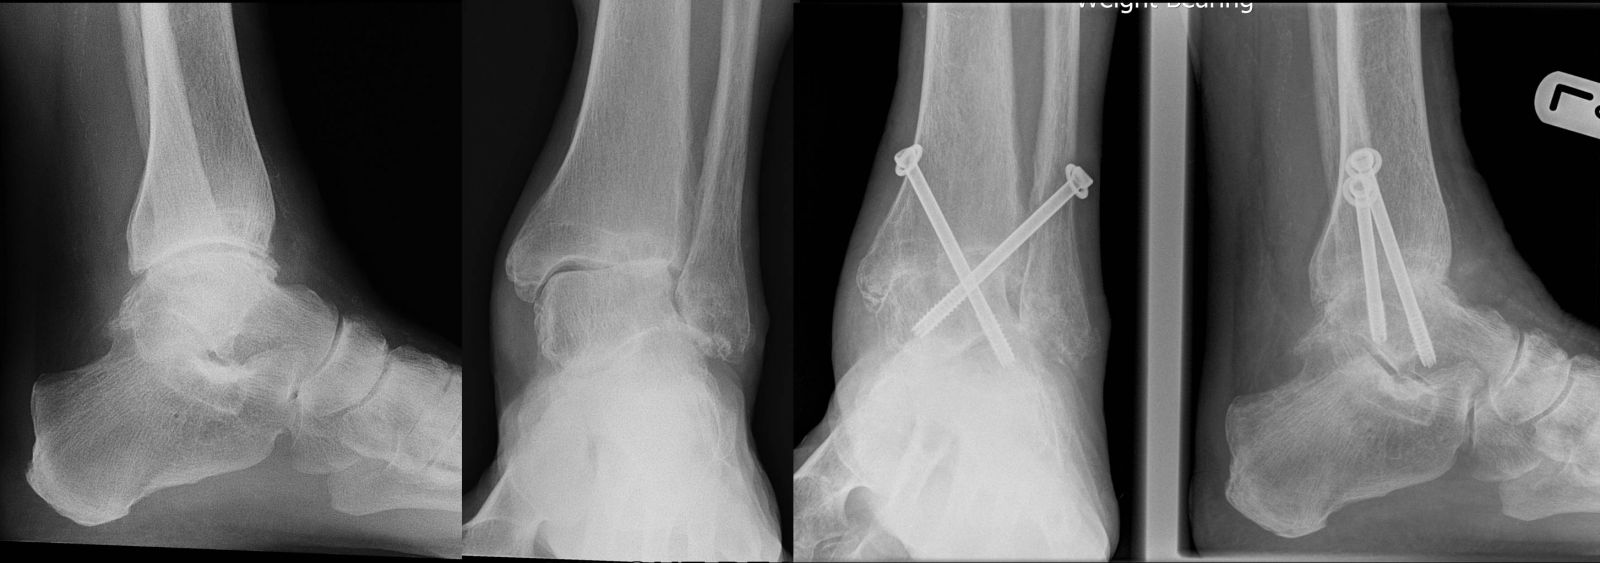

Αρθρόδεση Ποδοκνημικής

Η αρθρόδεση καταργεί την κίνηση στην άρθρωση μεταξύ αστραγάλου και κνήμης (διατηρείται όμως η κίνηση σε παρακείμενες αρθρώσεις). Σε γενικές γραμμές χάνεται περίπου 50% από την κάμψη-έκταση του ποδιού ως προς την κνήμη. Έχει ένδειξη για τελικού σταδίου αρθρίτιδα, όταν όλα τα άλλα μέτρα αποτυγχάνουν να ελέγξουν τον πόνο. Αντενδείξεις πρακτικά δεν υπάρχουν. Καθώς η επέμβαση μπορεί να γίνει αρθροσκοπικά , ακόμα και προβλήματα στο δέρμα (ουλές, φλεβική ανεπάρκεια) ή παθήσεις όπως διαβήτης, αρτηριοπάθεια δεν αποτελούν ιδιαίτερο πρόβλημα για το χειρουργό και τον ασθενή.

Η εξέλιξη της χειρουργικής τεχνικής τα τελευταία χρόνια επιτρέπει η επέμβαση να γίνει αρθροσκοπικά (με μικρές τομές), κάτι που γίνεται από την ομάδα μας με επιτυχία. Η επέμβαση γίνεται με γενική ή ραχιαία αναισθησία και απαιτεί την παραμονή στην κλινική για 2-3 μέρες. Στην επέμβαση αυτή γίνεται οστεοσύνθεση με βίδες ανάμεσα στον αστράγαλο και την κνήμη, αφού καθαριστούν οι αρθρικές επιφάνειες από τον υπολειπόμενο παθολογικό χόνδρο και τα οστεόφυτα. Μετά το χειρουργείο χρησιμοποιείται γύψος για 3-5 μήνες ανάλογα με την πορεία πώρωσης που ελέγχεται ακτινολογικά (στις 6 εβδομάδες, 3 μήνες, 5 μήνες). Στις 6 εβδομάδες ο ασθενής αρχίζει να φορτίζει το σκέλος (μέσα στο γύψο), ενώ μετά τους 3 μήνες μπορεί να χρησιμοποιηθεί αφαιρούμενος νάρθηκας (΄΄μπότα΄΄) επιτρέποντας τη φόρτιση. Η αρθροσκοπική αρθρόδεση σχετίζεται με μικρότερη επιβάρυνση για τον ασθενή. Αποφεύγονται οι μεγάλες χειρουργικές τομές, γεγονός που μειώνει το ποσοστό των επιπλοκών (όπως λοιμώξεις, μη πώρωση, κακή επούλωση χειρουργικής τομής) και επιταχύνει την πώρωση και την επάνοδο στις δραστηριότητες, με πολύ καλά λειτουργικά αποτελέσματα σε ποσοστό πάνω από 95%. Ο πόνος φεύγει και παρόλο που η κίνηση μειώνεται σε κάποιο βαθμό οι ασθενείς είναι ευχαριστημένοι αφού μπορούν να χρησιμοποιούν και να φορτίζουν το πόδι τους πολύ καλύτερα και ανώδυνα. Σπάνια χρειάζεται η κατασκευή ειδικής κυρτής σόλας στο παπούτσι για να διευκολύνει την κίνηση. Γενικά οι ασθενείς με αρθρόδεση ποδοκνημικής μπορούν να συμμετέχουν στις καθημερινές δραστηριότητες χωρίς πρόβλημα, να οδηγούν και να κάνουν και βαριά χειρονακτική εργασία. Σε ότι αφορά τις αθλητικές δραστηριότητες, είναι δυνατό να επανέλθουν στο επίπεδο που είχαν πριν την επέμβαση. Είναι δυνατό το κολύμπι, το ποδήλατο, το σκι, αλλά όχι αθλήματα όπως ποδόσφαιρο, μπάσκετ, τένις, που απαιτούν αλλαγές στην πορεία της κίνησης και γενικά ευλυγισία. Επειδή στους ασθενείς που χρειάζονται αρθρόδεση, η δυσκαψία και ο πόνος έχουν περιορίσει τις δυνατότητες τους για άσκηση αρκετά χρόνια πριν το χειρουργείο, το ανώδυνο πόδι μετεγχειρητικά βελτιώνει την ποιότητα ζωής και τις δραστηριότητές τους.